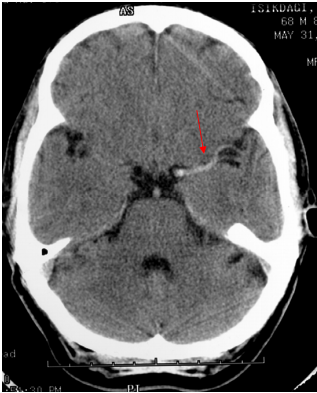

TDM (Scanner) Cérébral: L’Hémorragie apparait comme une hyperdensité spontannée (blanc) dans le parenchyme ou les ventricules

- Hémorragie cérébro-méningée avec inondation ventriculaire: